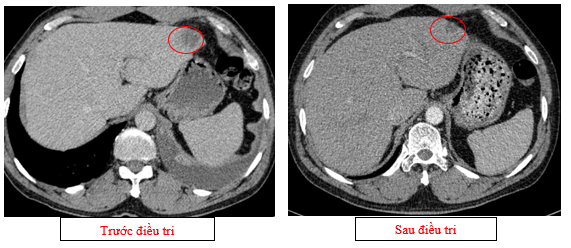

- Chụp cắt lớp vi tính ổ bụng (08/2025): Nhu mô gan phải có vài nốt, nốt lớn nhất hạ phân thùy VII có nốt giảm tỷ trọng, ngấm thuốc kém sau tiêm đường kính 24mm, hạ phân thùy II, III có nốt 2 giảm tỷ trọng đường kính 13mm và 27mm. Các ổ đặc xương rải rác đốt sống ngực thắt lưng, xương cùng và xương chậu hai bên – theo dõi tổn thương thứ phát

Hình 04: Nhu mô gan phải có vài nốt, nốt lớn nhất hạ phân thùy VII có nốt giảm tỷ trọng, ngấm thuốc kém sau tiêm đường kính 24mm, hạ phân thùy II, III có nốt 2 giảm tỷ trọng đường kính 13mm và 27mm

Hình 05: Các ổ đặc xương rải rác đốt sống ngực thắt lưng, xương cùng và xương chậu hai bên – theo dõi tổn thương thứ phát

- Chụp cắt lớp vi tính ổ bụng (11/2025): Nhu mô gan phải có vài nốt, nốt lớn nhất hạ phân thùy VII có nốt giảm tỷ trọng, ngấm thuốc kém sau tiêm đường kính 8mm, hạ phân thùy II, III có nốt giảm tỷ trọng đường kính (tổn thương giảm đáng kể so với phim chụp ngày 08/2025). Các ổ đặc xương rải rác đốt sống ngực thắt lưng, xương cùng và xương chậu hai bên

Hình 11: Tổn thương ngấm thuốc kém nhu mô gan hạ phân thùy II giảm đáng kể kích thước

Hình 12: Tổn thương ngấm thuốc kém nhu mô gan hạ phân thùy VII giảm đáng kể kích thước

- Các tổn thương ngấm thuốc kém do di căn tại gan giảm kích thước đáng kể (27mm còn 8mm)